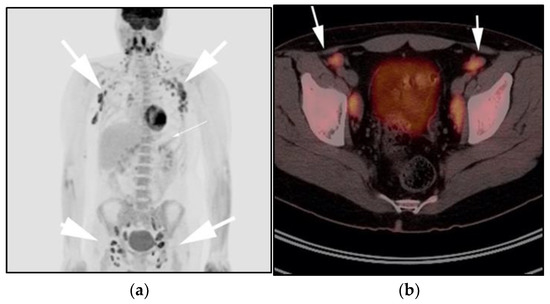

Imaging is not necessary to establish a diagnosis of ALPS but might aid in its diagnostic evaluation. Stability in the size of lymphadenopathy and hepatosplenomegaly over many years may suggest ALPS from other malignant lymphoproliferative diseases [26] (Figure 4).

Figure 4.

A 30-year-old male with known history of autoimmune lymphoproliferative disorder since childhood. (a) Maximal intensity projection (MIP) FDG PET/CT image shows generalized hypermetabolic lymphadenopathy throughout the head, neck, chest, abdomen, and pelvis (white arrows). Note that splenic activity is not visualized (thin white arrow) because the spleen was surgically removed during childhood due to splenomegaly. (b) Axial FDG PET image shows hypermetabolic adenopathy within pelvis mainly about the bilateral pelvic side wall and external iliac nodes (white arrows). Lymph nodes often show little or only modest uptake, a clue, in addition to stability of nodal size and over multiple time points. Biopsy is the only method for definitive diagnosis. (c) H&E section of a lymph node shows highly proliferative paracortical expansion composed of small proliferative lymphocytes and immunoblasts with preserved lymphoid follicular architecture. There is sinus histiocytosis. (Original magnification 400×, H&E stain).

Once the diagnosis of ALPS is established, baseline and periodic follow-up CT scans should therefore be obtained to document the stability of lymphadenopathy and hepatosplenomegaly. 18F-FDG PET/CT may also be helpful because mild to moderate FDG uptake is typical of ALPS compared to the high FDG uptake characteristic of malignant lymphomas. By evaluating for areas of high FDG uptake, 18F-FDG PET/CT may help in the early detection of lymphoma transformation and demonstrate the best site for biopsy, when indicated [23]. Awareness of ALPS is pivotal because ALPS often requires long-term immunosuppressive therapies as opposed to chemotherapy that is standard for malignant lymphoproliferative disorders.